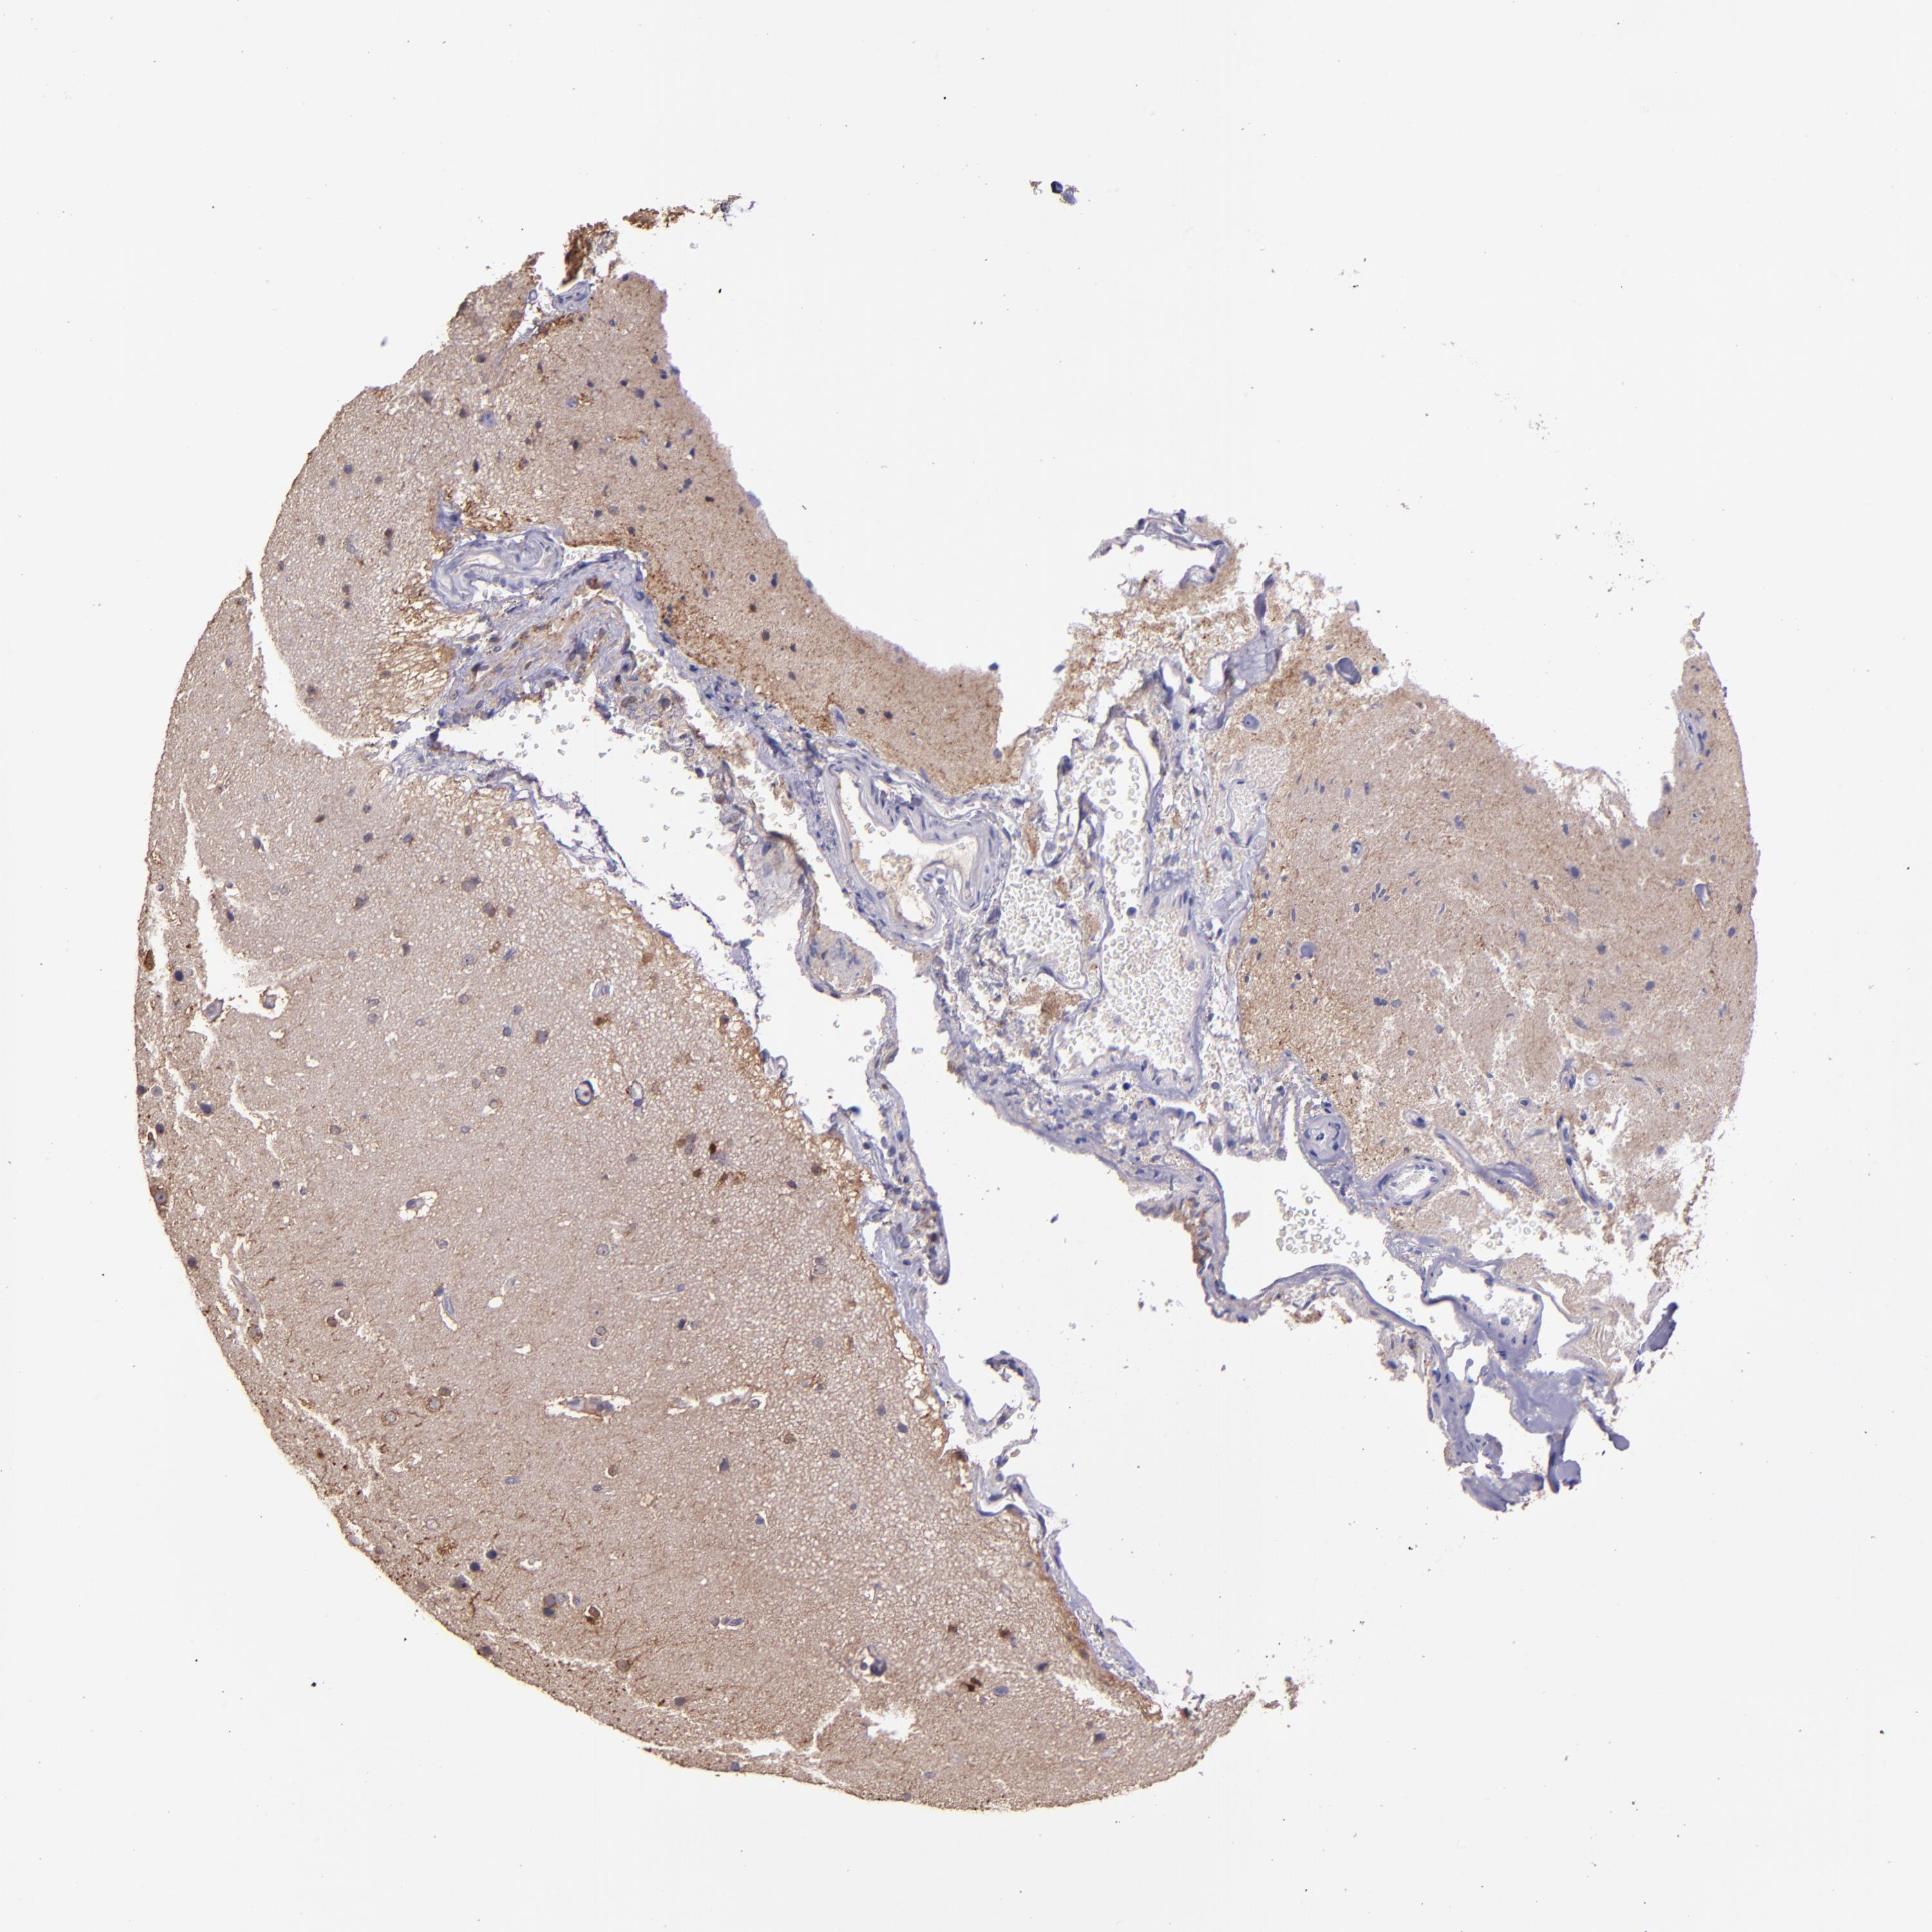

GLIOMA - Protein expressioni

A mouse-over function shows sample information and annotation data. Click on an image to view it in a full screen mode. Samples can be filtered based on level of antibody staining by selecting one or several of the following categories: high, medium, low and not detected. The assay and annotation is described here.

Note that samples used for immunohistochemistry by the Human Protein Atlas do not correspond to samples in the TCGA dataset.

Antibody stainingi

Antibody staining in the annotated cell types in the current human tissue is reported as not detected, low, medium, or high, based on conventional immunohistochemistry profiling in selected tissues. This score is based on the combination of the staining intensity and fraction of stained cells.

Each image is clickable and will lead to virtual microscopy that enables deeper exploration of all samples and also displays staining intensity scores, fraction scores and subcellular localization as well as patient and tissue information for each sample.

Antibody HPA001667

Antibody CAB016724

Staining

High

Medium

Low

Not detected

Intensity

Strong

Moderate

Weak

Negative

Quantity

>75%

75%-25%

<25%

None

Location

Nuclear

Cytoplasmic/membranous

Cytoplasmic/membranous,nuclear

Glioma, malignant, High grade

Glioma, malignant, Low grade

Glioma, malignant, NOS